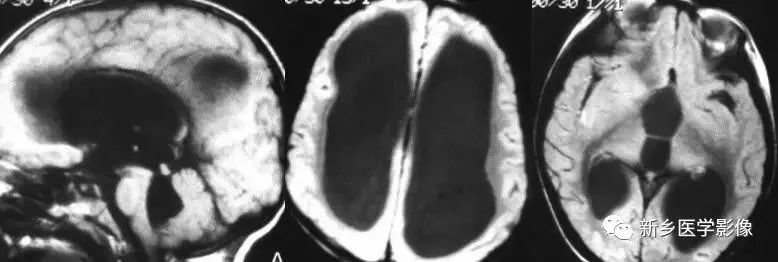

前脑无裂畸形(holoprosencephaly):

是指一系列位于中线程度不同的畸形,累及大脑、面部、脑于和小脑。前脑未能够分开,呈不全性或完全性,端脑和间脑无法区分。根据脑及面部畸形程度将其分为无叶型、半叶型和单叶型。

- 无叶型前脑无裂畸形:最严重,端脑半球间没有裂隙,呈马蹄形或新月形扩大的单脑室跨越中线,与背侧囊交通。丘脑互相融合,面部畸形可有两眼距离过近、独眼畸形等。往往死于胎儿或新生儿期。

- 半叶型前脑无裂畸形:在前脑可见部分裂隙, 形成不同发育程度的大脑纵裂及大脑镰。两侧大脑半球在前部未完全分开,但枕叶和 双侧侧脑室体部分离,丘脑分开不完全。三脑室和海马发育不全,胼胝体仅可见到压部,而其他部分缺如额叶和基底节前部分辨不清。临床表现有两眼距离过近、唇裂、腭裂等面部畸形,侧脑室呈单一性且明显扩大。

- 单叶型前脑无裂畸形:与正常发育脑仅有些很小的区别,如透明隔缺如或双侧额叶不完全分开。